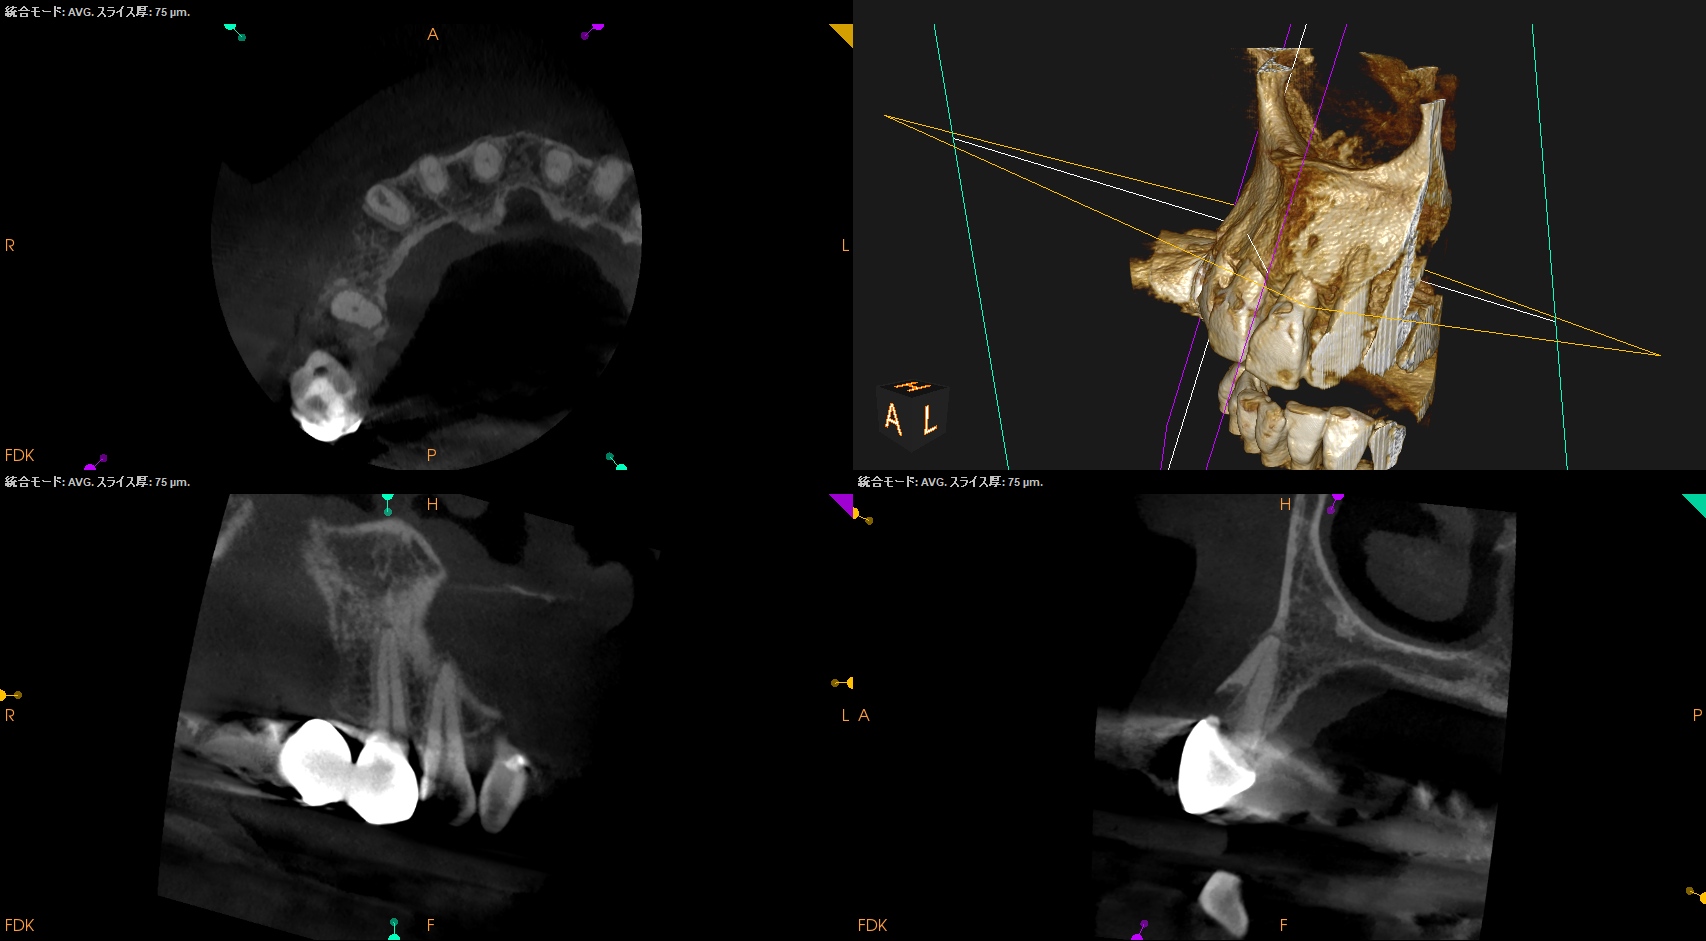

また根管治療する際は、

RIL(Radiographic Instrumentation Length)は23mm程度であるが、

クラウンの切端に穴を開けて根管治療をしなければならず、これは現実的には無理だろう。

なぜならば、患者さんはこのブリッジを外す・壊すことに抵抗感が強いからだ。

となれば、根管治療をせずにApicoectomyに移行する可能性はあるだろう。